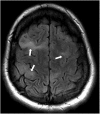

Hamartomas are tumours composed of mesenchymal tissues such as cartilage, fat, connective tissue and smooth muscle and can be found in virtually any organ system. These masses commonly develop sporadically, but are also seen in certain syndromes such as tuberous sclerosis or Carney triad. While their imaging appearance varies depending on the organ they arise from, findings are usually unique and a diagnosis can be confidently made. Radiologists must be aware of the clinical and imaging presentations of these lesions with the particular goal of avoiding unnecessary studies or invasive procedures. Furthermore, knowledge of common syndromic entities is crucial, as the radiologist may be the first to suggest the diagnosis.